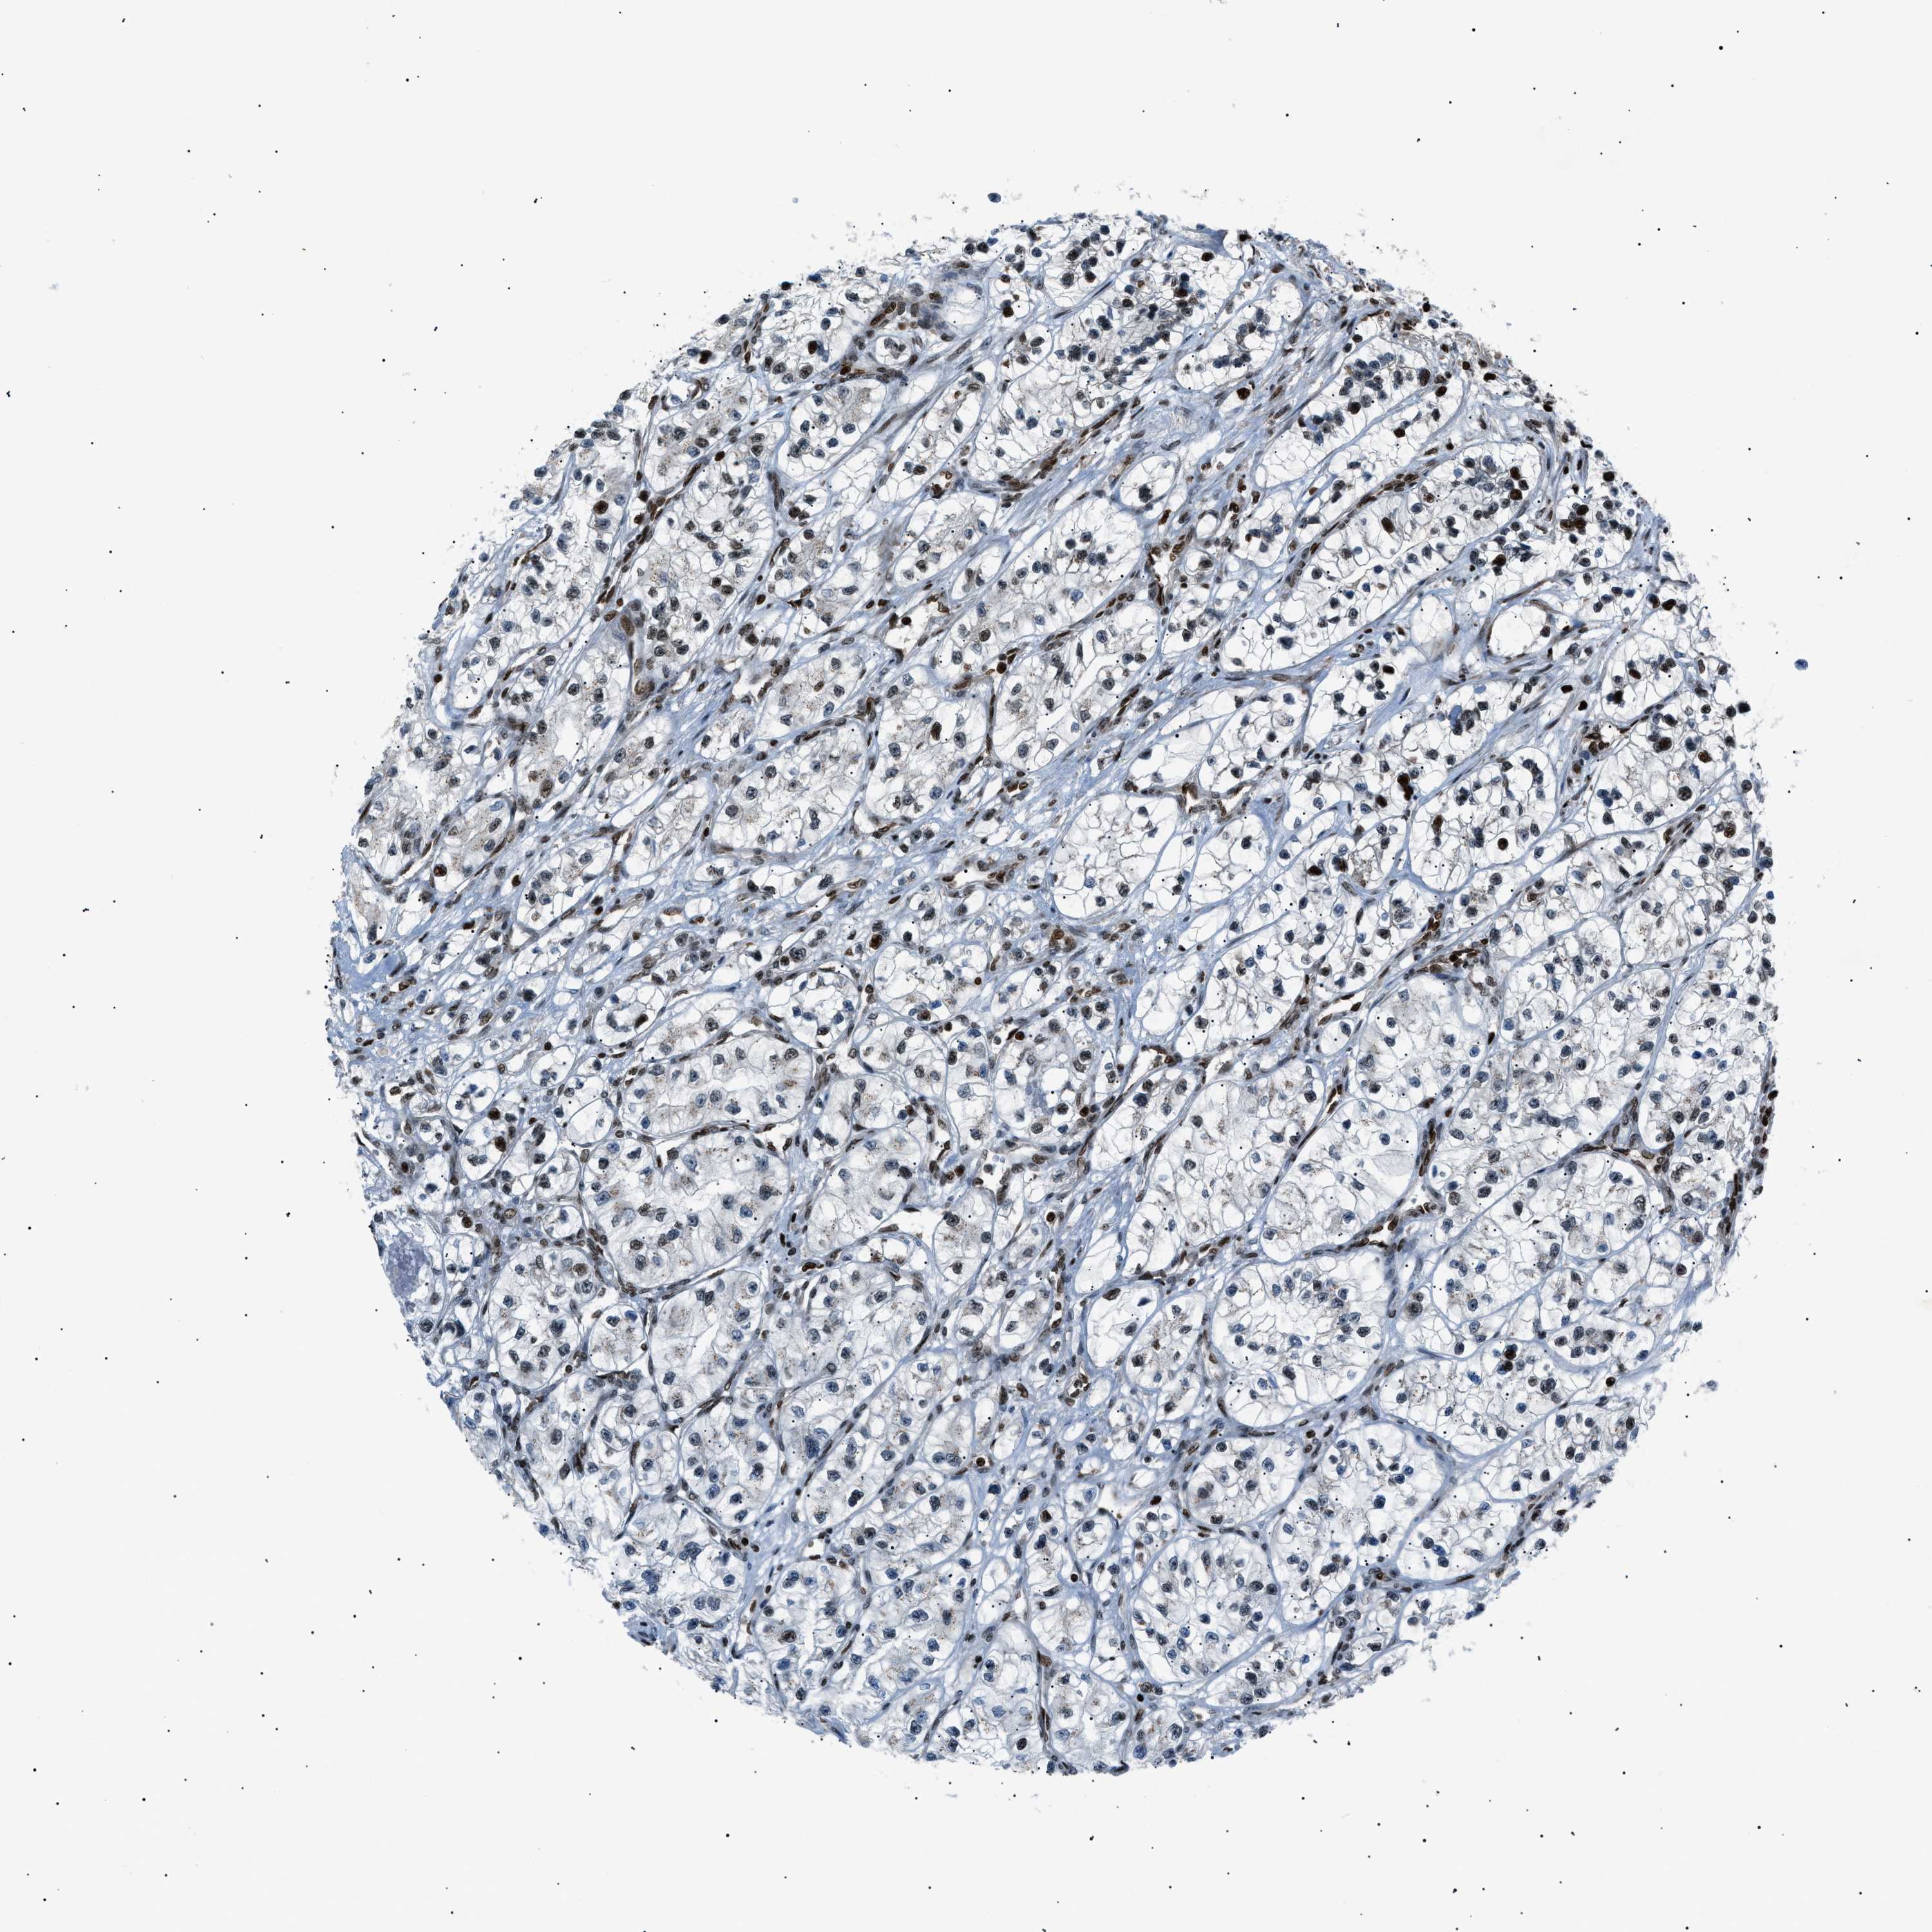

KIDNEY RENAL PAPILLARY CELL CARCINOMA (TCGA) - Interactive survival scatter ploti

The Survival Scatter plot shows the clinical status (i.e. dead or alive) for all individuals in the patient cohort, based on the same data that underlies the corresponding Kaplan-Meier plots. Patients that are alive at last time for follow-up are shown in blue and patients who have died during the study are shown in red.

The x-axis shows the expression levels (FPKM) of the investigated gene in the tumor tissue at the time of diagnosis. The y-axis shows the follow-up time after diagnosis (years). Both axes are complimented with kernel density curves demonstrating the data density over the axes. The top density plot shows the expression levels (FPKM) distribution among dead (red) and alive patients (blue). The right density plot shows the data density of the survived years of dead patients with high and low expression levels respectively, stratified using the cutoff indicated by the vertical dashed line through the Survival Scatter plot. This cutoff is automatically defined based on the FPKM cutoff that minimizes the p-score. The cutoff can be changed by dragging the vertical line or by entering a cutoff value in the square labeled "Current cut-off".

Under the Survival Scatter plot the p-score landscape (black curve; left axis) is shown together with dead median separation (red curve; right axis). Dead median separation is the difference in median mRNA expression between patients who have died with high and low expression, respectively. It is calculated as follows: median FPKM expression of dead patients with high expression - median FPKM expression of dead patients with low expression. This is intended to aid the user in visually exploring custom cutoffs and the associated p-scores and dead median separation.

Individual patient data is displayed and can be filtered by clicking on one or more of the category buttons on the top of the page. Categories describing expression level and patient information include: high, low, alive, dead, female, male and tumor stages. The scale of the x-axis can be toggled between linear and log-scale by clicking on the "x log" button. Mouse-over function shows TCGA ID, patient information and mRNA expression (FPKM) for each patient.

& Survival analysisi

Kaplan-Meier plots summarize results from analysis of correlation between mRNA expression level and patient survival. Patients were divided based on level of expression into one of the two groups "low" (under cut off) or "high" (over cut off). X-axis shows time for survival (years) and y-axis shows the probability of survival, where 1.0 corresponds to 100 percent.

PRKX is not prognostic in Kidney Renal Papillary Cell Carcinoma (TCGA)